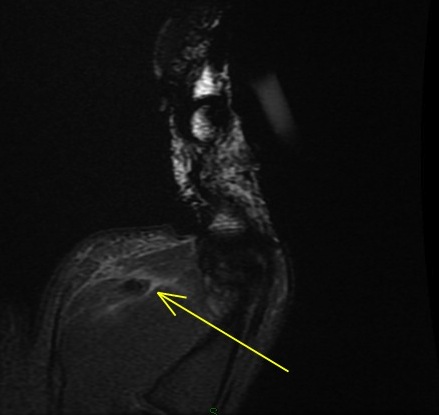

Figure 2 for case Flexor pollicis longus tendon ( RID2383 ) laceration

Figure 2